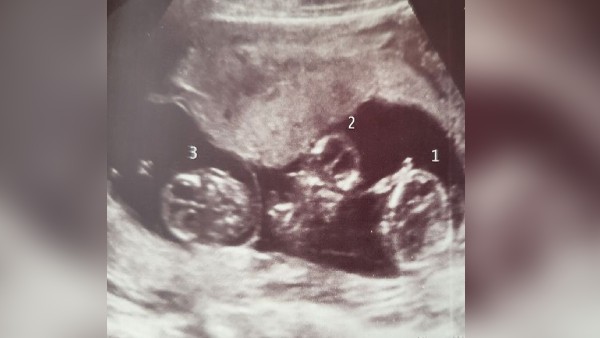

नॉटिंघम, 04 जून: आपने एक साथ पैदा होने वाले 3 बच्चों के बारे में बहुत सुना होगा, लेकिन ब्रिटेन की एक महिला ने 2 करोड़ में एक बार पैदा होने वाले एक जैसे 3 बच्चों को जन्म दिया है। यूके के नॉटिंघम में पहली बार मां बनी 28 वर्षीय जहरा अमीराबादी ने दिसंबर 2021 में अपनी तीन बेटियां रोया, अदीना और सेफिया को जन्म दिया। ऐसे जैसे दिखने वाले इन बच्चों को 'स्पॉन्टेनियस आइडेंटिकल ट्रिपलेट' कहा जा रहा है। जहरा और उनके पार्टनर अशरफ रीड को प्रेगनेंसी के 12 हफ्ते के स्कैन में तीनों बच्चों के बारे में पता लगा था।

तीनों बच्चियां अब पांच महीने की हैं। जहरा ने बताया कि तीन बच्चों में से दो प्लेसेंटा शेयर कर रहे थे, जबकि सेफिया अपने दम पर थी। बता दें कि प्लेसेंटा वो जगह होती है, जो मां के गर्भ में बच्चे को सुरक्षा और पोषण दोनों उपलब्ध कराती है। जहरा के मुताबिक डॉक्टरों को शुरू में लगा कि उनके एक जैसे जुड़वां बच्चे हैं - एक लड़का और एक लड़की। उन्होंने 17वीं स्कैन में पुष्टि की कि वे सभी लड़कियां थीं।

मिरर से बात करते हुए महिला ने कहा, "जब वे पैदा हुए थे तो वे एक जैसे दिखते थे, इसलिए हमने एक टेस्ट किया और यह दिखाया कि वे सभी समान थे। उन्होंने बताया कि रोया-अदीना की नाल एक थी, जबकि सेफिया की नाल अलग थी। जहरा ने खुलासा किया कि वह अपनी गर्भावस्था के दौरान लगातार थकी हुई थी, दिन में दो बार झपकी लेती थी, और कहा कि मैं रात में सोने के लिए संघर्ष करती थी। उन्होंने कहा कि मेरे 24 हफ्ते के स्कैन में डॉक्टर ने कहा कि मैं 37 हफ्ते के बच्चे के बराबर ले जा रही थी।